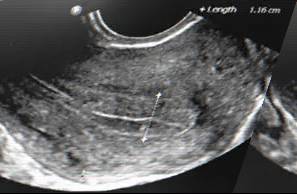

7. 解冻胚胎移植前很多次抽血、B超的目的是什么?这个过程中为什么有的人需要用药,有的人不需要用药?

答:解冻移植前抽血、B超的目的是监测排卵或者监测内膜的厚度,排卵后或内膜达到一定厚度才解冻胚胎。这个过程中,如果患者有卵泡发育并且排卵,那么一般不需要额外用药,称作“自然周期”;如果没有大卵泡发育,那就需要采用雌激素促进内膜生长,称作“人工周期”,常用的雌激素包括口服的补佳乐、塞阴道的芬吗通、外用涂皮肤的爱斯妥。